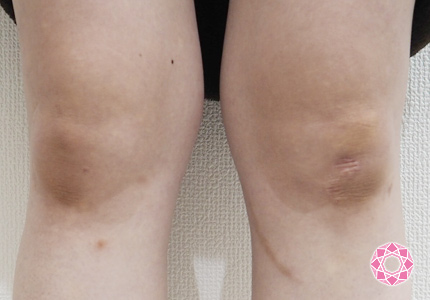

足の皮膚が茶色くなる原因は?下肢静脈瘤による色素沈着と手術の必要性を専門医が解説下肢静脈瘤の原因・症状・治療方法・予防方法などを専門医が解説。

専門医が解説 下肢静脈瘤の硬化療法後に起こる色素沈着とは?原因と対策を詳しく紹介下肢静脈瘤の原因・症状・治療方法・予防方法などを専門医が解説。

Q&A 足の色素沈着は、静脈瘤を治療すれば治るの?目黒外科東京都品川区・目黒駅から徒歩30秒。